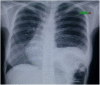

We present a rare case of 32year old female with congenital diaphragmatic eventeration female presenting in an adult. She had symptoms of intermittent dyspnea and occasional epigastric discomfort. Patient had no previous history of trauma. Physical examination showed bowel sound involving the left hemithorax. Imaging modalities confirmed the diagnosis of a congenital left diaphragmatic eventeration. Patient underwent plication of the diaphragm using the abdominal approach. Intra-operatively, the left diaphragm was attenuated. Plication was done with 1st layer of imbricating silk heavy sutures buttressed by a second layer of interrupted absorbable sutures. She post-operatively had atelectasis on the left lung. Incentive spirometry and deep breathing exercises were started with resolution of the atelectasis after 1 week post-operatively. Patient had an unremarkable post-operative stay with resolution of symptoms. There are reports that diaphragmatic eventration diagnosed even as late 70 years old, highlighting the dogma that this is an asymptomatic disorder does not need all the time surgical therapy. But we still recommend surgical therapy as soon as diagnosis is confirmed. In this patient, there was no recurrence of symptoms after a follow-up of 2 years. Whether surgery indeed improved lung functions in these vastly asymptomatic patients, these questions could be an active area of research in the long term outcomes of these patients.